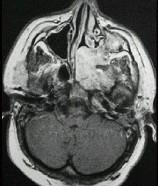

问题 男性,19岁,左侧鼻腔反复出血1年余,CT、MRI扫描如图所示,请选择最可能诊断()

选项 A.鼻息肉 B.鼻咽腔脓肿 C.鼻咽部青年纤维血管瘤 D.鼻咽癌 E.鼻咽部淋巴瘤

答案 C